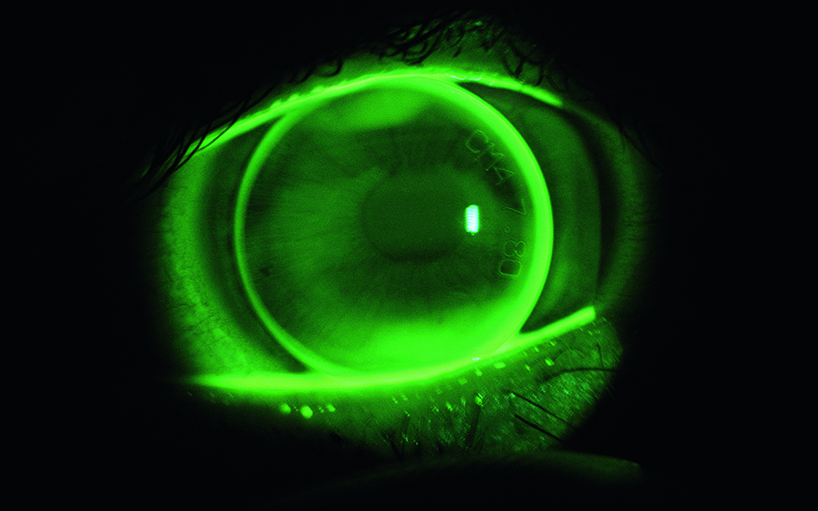

• DCT lens

DCT lens

DCT-Lens.jpg

teaser_dct-lens.jpg